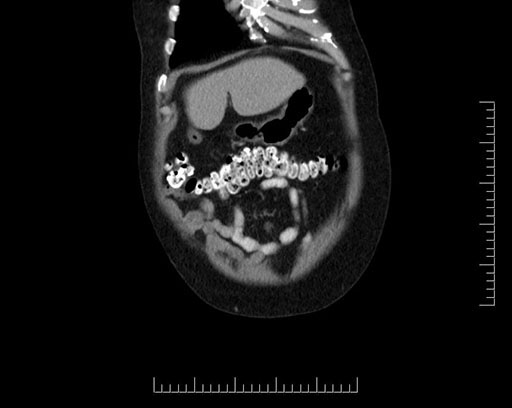

Whipple (pancreaticoduodenectomy) [case 7]

Imaging Analysis

Look through the patient's CT scan to identify any areas of concern for the necessary procedure.

Based on your CT findings, which issue(s) would give reason for "planned slowing down moment(s)" in this case?

Considering a standard Whipple procedure, what step(s) of the operation would you do differently in this case?